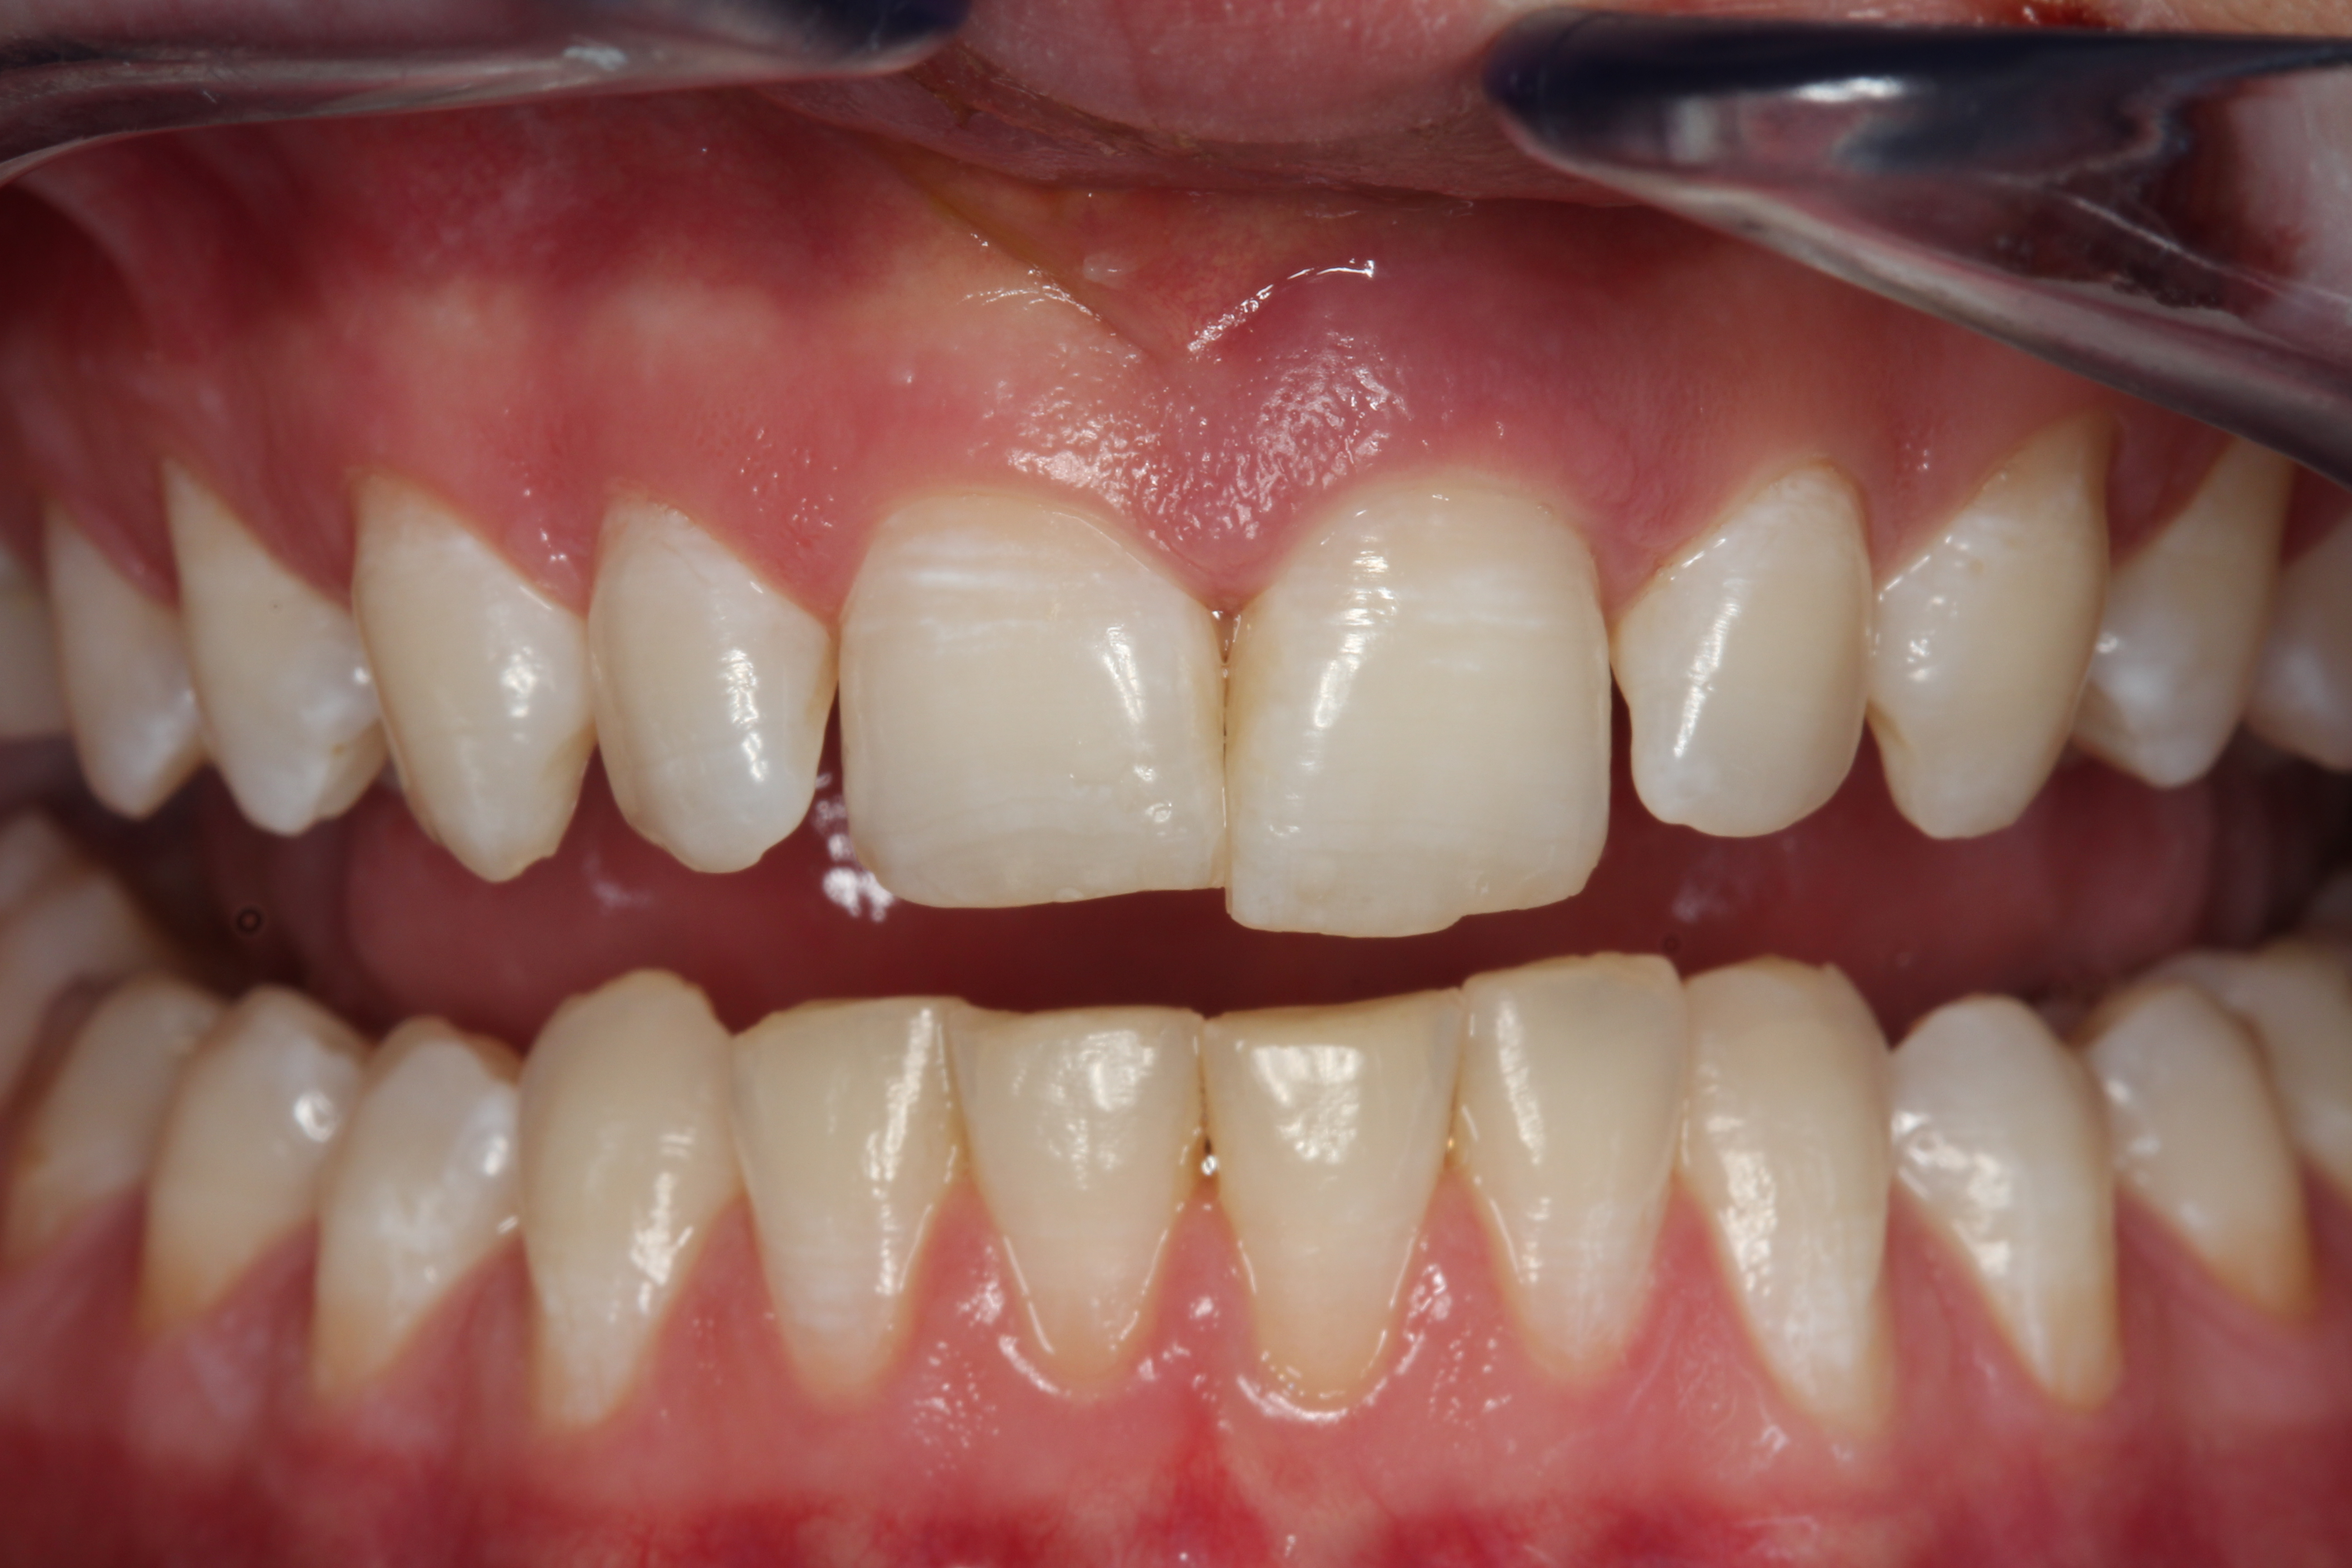

A young man presented with a fractured maxillary left-central incisor on a Monday morning after a Saturday evening discussion that did not end well (Figure 1). Visual oral examination and palpation of the structures revealed mobility of 3+, pain on palpation and percussion, a thick soft-tissue profile, and a low lip line. Gingival zeniths were irregular, there was a class II division 2 deep bite, and the periodontium was healthy overall (Figure 2 through Figure 4). Radiographs requested at the time of the initial visit were periapicals, panoramic, and CBCT images (Figure 5 and Figure 6). After all images and information were reviewed and the extent of his injury was discussed, the patient was presented with the following options: removable prosthetics, fixed partial denture, extract and do nothing, or extract and place a dental implant with bone augmentation.

Fig 3. Retracted photograph, teeth apart.

Figure 3